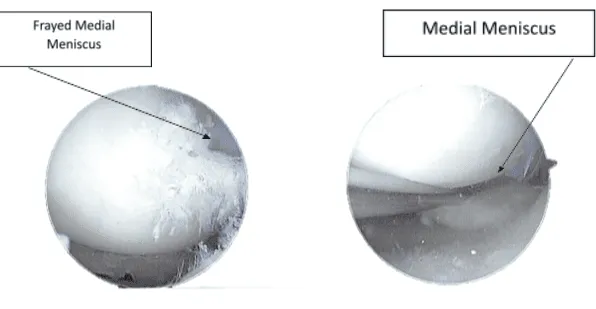

Se realizaron radiografías y resonancias magnéticas en la consulta. Se encontró desgarro vertical en el borde libre del menisco medial del cuerno posterior, con un leve deshilachamiento en la parte inferior inferior/borde libre del segmento corporal. Pérdida condral leve del compartimento femorotibial medial. Desgaste condral leve del compartimento patelofemoral, preferentemente sobre la parte medial del compartimento.

Se introdujo una sonda. Se observó la rotura del menisco medial atravesando el cuerpo y el cuerno posterior hasta la raíz. Se introdujo la afeitadora y se limpiaron los márgenes. Se usaron el mordedor ascendente y el mordedor recto para eliminar el menisco degenerado a lo largo del borde interior del menisco medial. El endoscopio se trasladó a la muesca intercondilar, donde se encontró que el LCA estaba intacto con degeneración.

El endoscopio se trasladó nuevamente a la articulación patelofemoral, donde se encontró una lesión de grado 3 a 4 de OA en el cóndilo tibiofemoral medial en la región correspondiente. Se limpiaba con un mordador y una afeitadora. Se volvió a examinar la rodilla y se desbridó aún más el menisco medial.